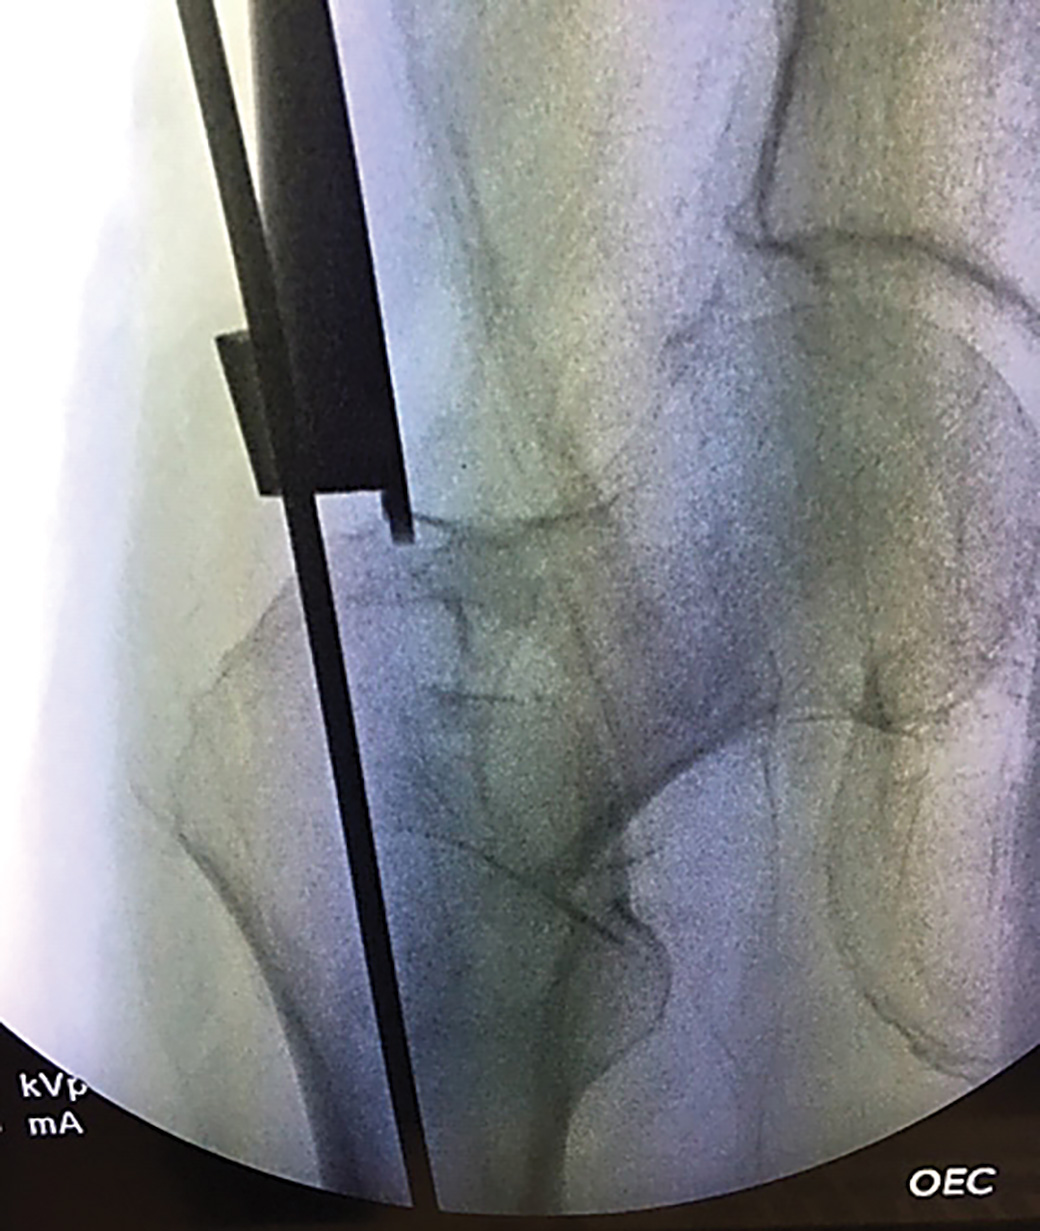

Retractor/guide designed for aiming guide wire when performing femoral nailing (TFN for an intertrochanteric fracture), ortibial nailing using the parapatellar approach

Dimensions Overall Length: 12″ 30,5 cm) Blade Width: .71″ (1,8 cm) Prong Length: 6 mm Guide Hole Diameter: 4,5 mm